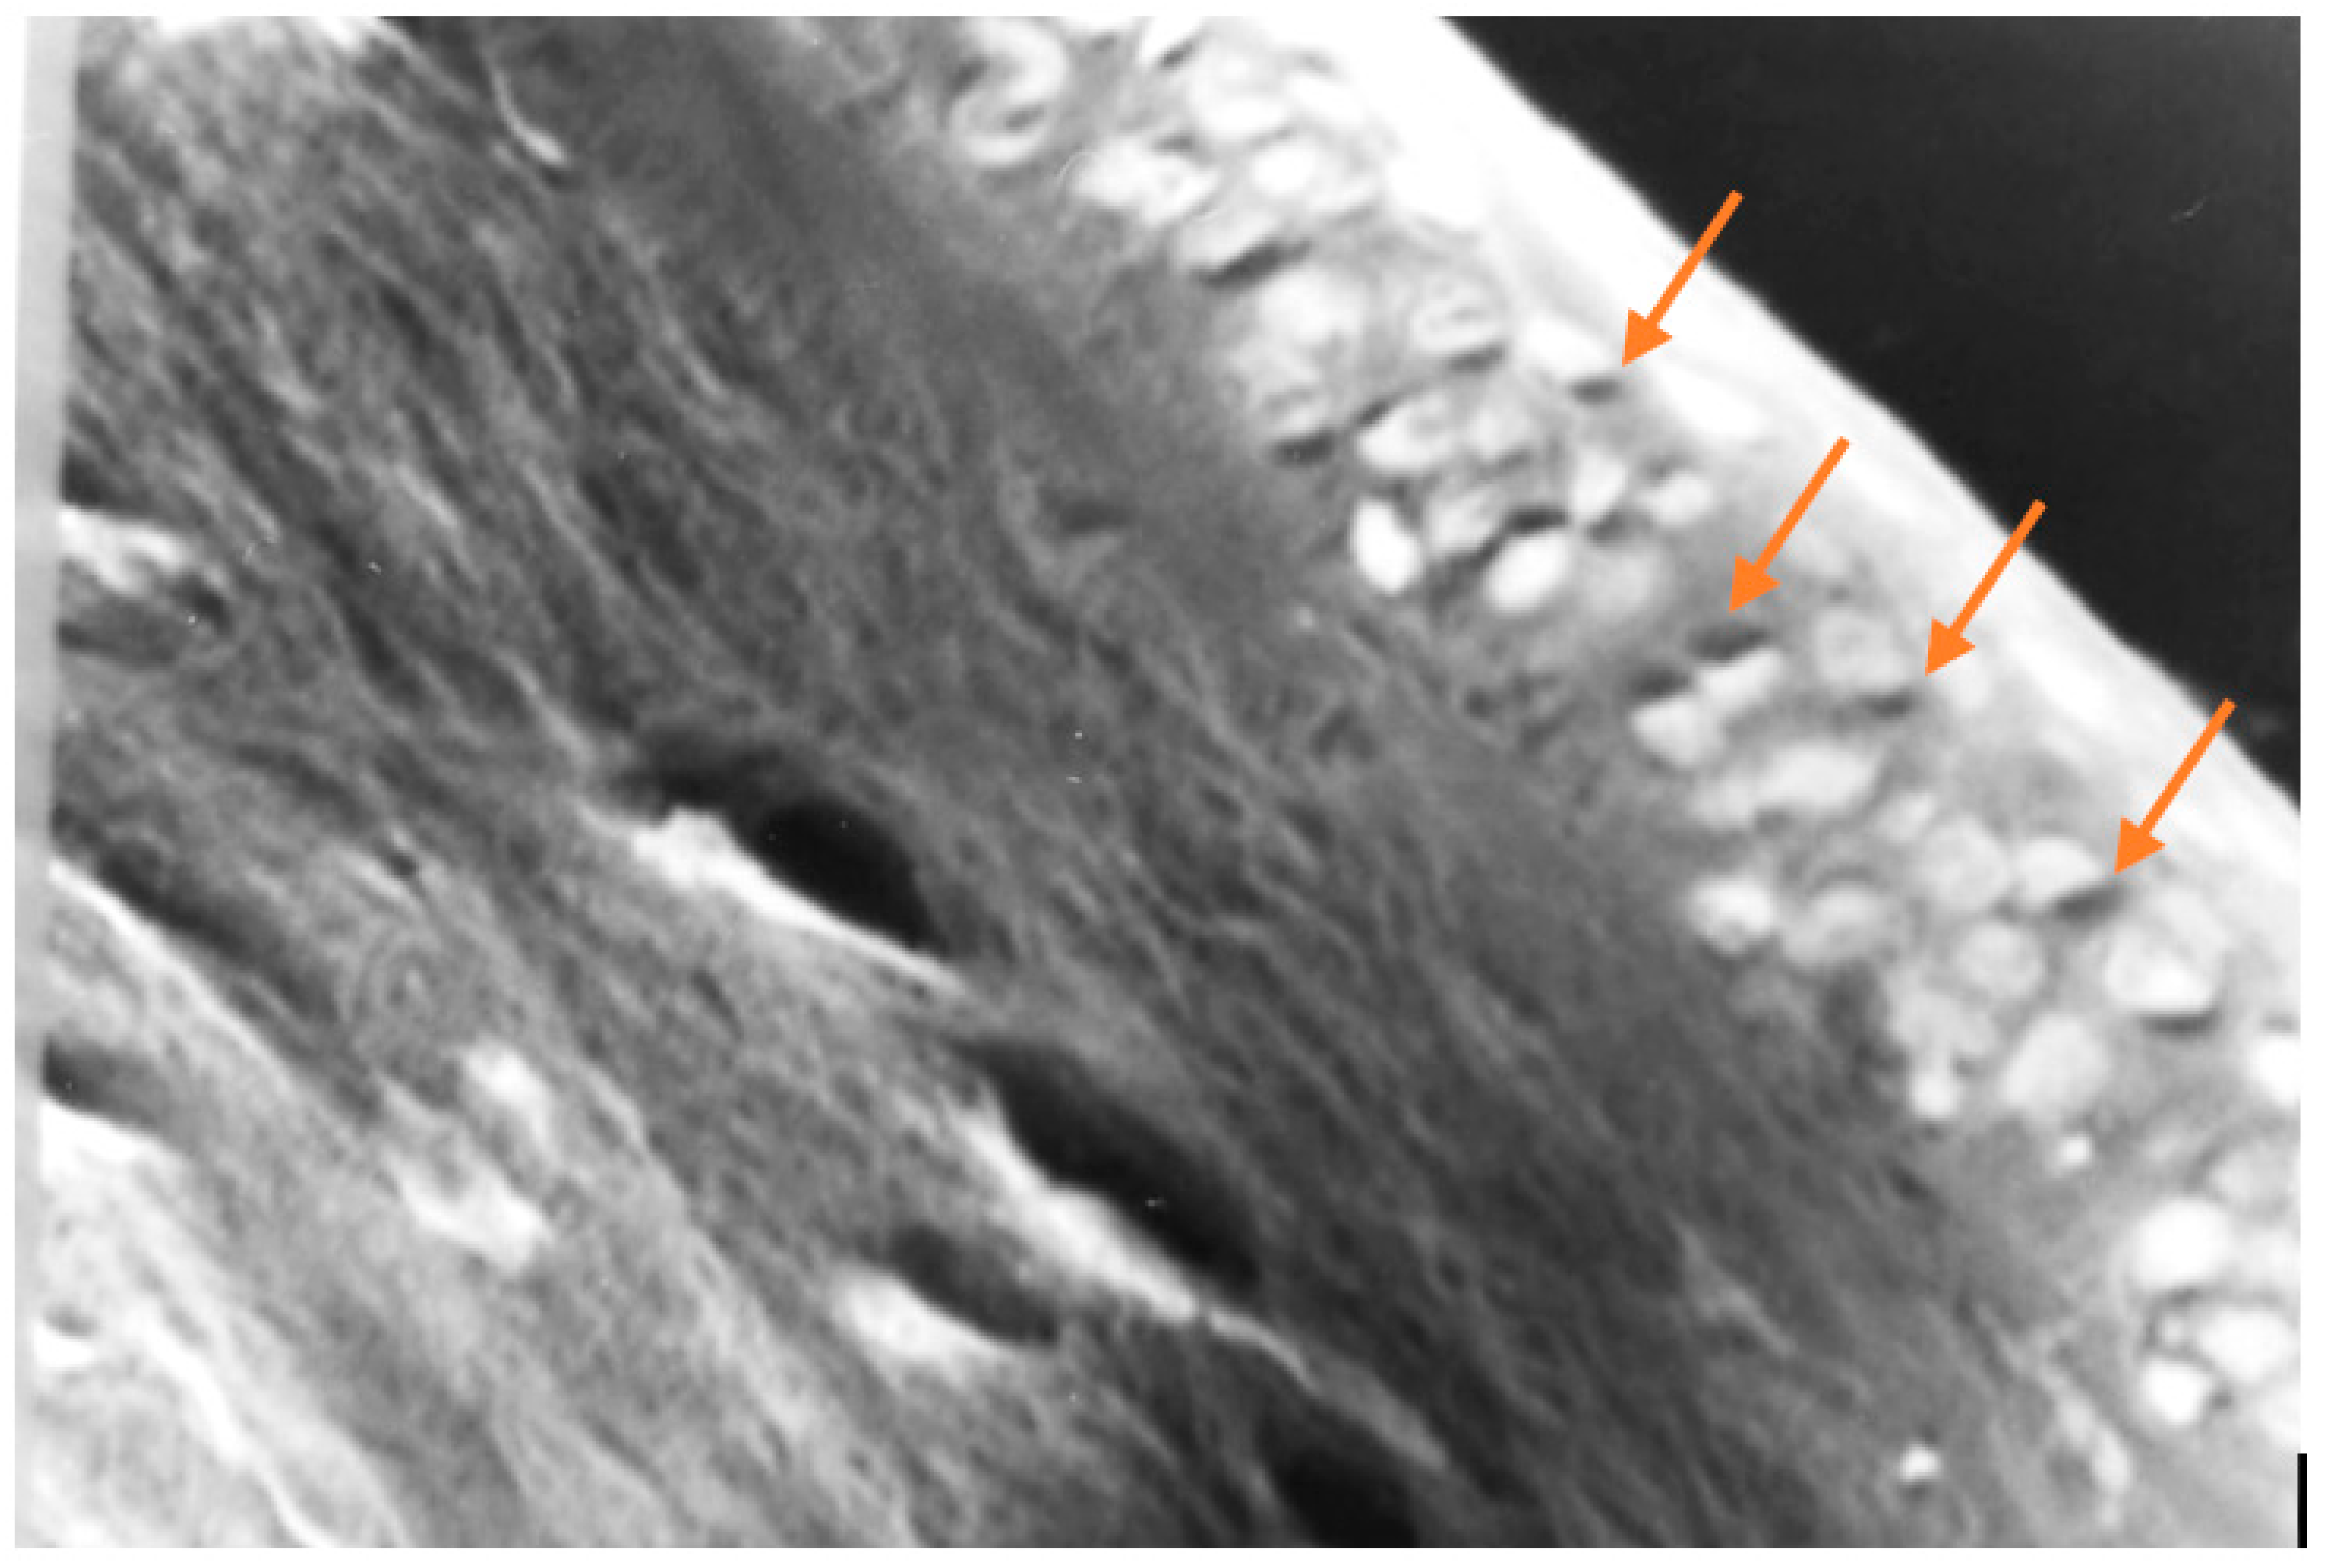

Figure 12. In this photomicrograph taken with a light microscope, and then digitally processed, the collagen fibers that make up the corneal stroma can be seen on the left, and on the right the cells that make up the epithelial layer of the cornea. The yellow arrows point to dark spots, within some epithelial cells, which could correspond to melanin. Melanin is not easy to identify under the microscope, not even by histochemistry. (100 X, H & E).